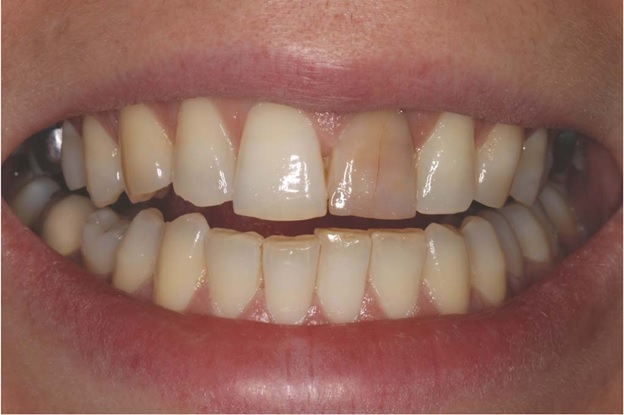

7 ) Плохая эстетика. Зуб окрашивается в розовато-коричневатый оттенок. На задних зубах это не так заметно, но передние выглядят… своеобразно. Резорцин плотно въедается в ткани, даже отбеливание не всегда работает. Часто прибегают к винирам или коронкам.

Именно поэтому резорцин стал визитной карточной советской карательной стоматологии на Западе, где от этого метода отошли намного раньше. Называют они такие зубы red russian teeth («красные русские зубы»). Из-за них спалилось немало советских разведчиков!